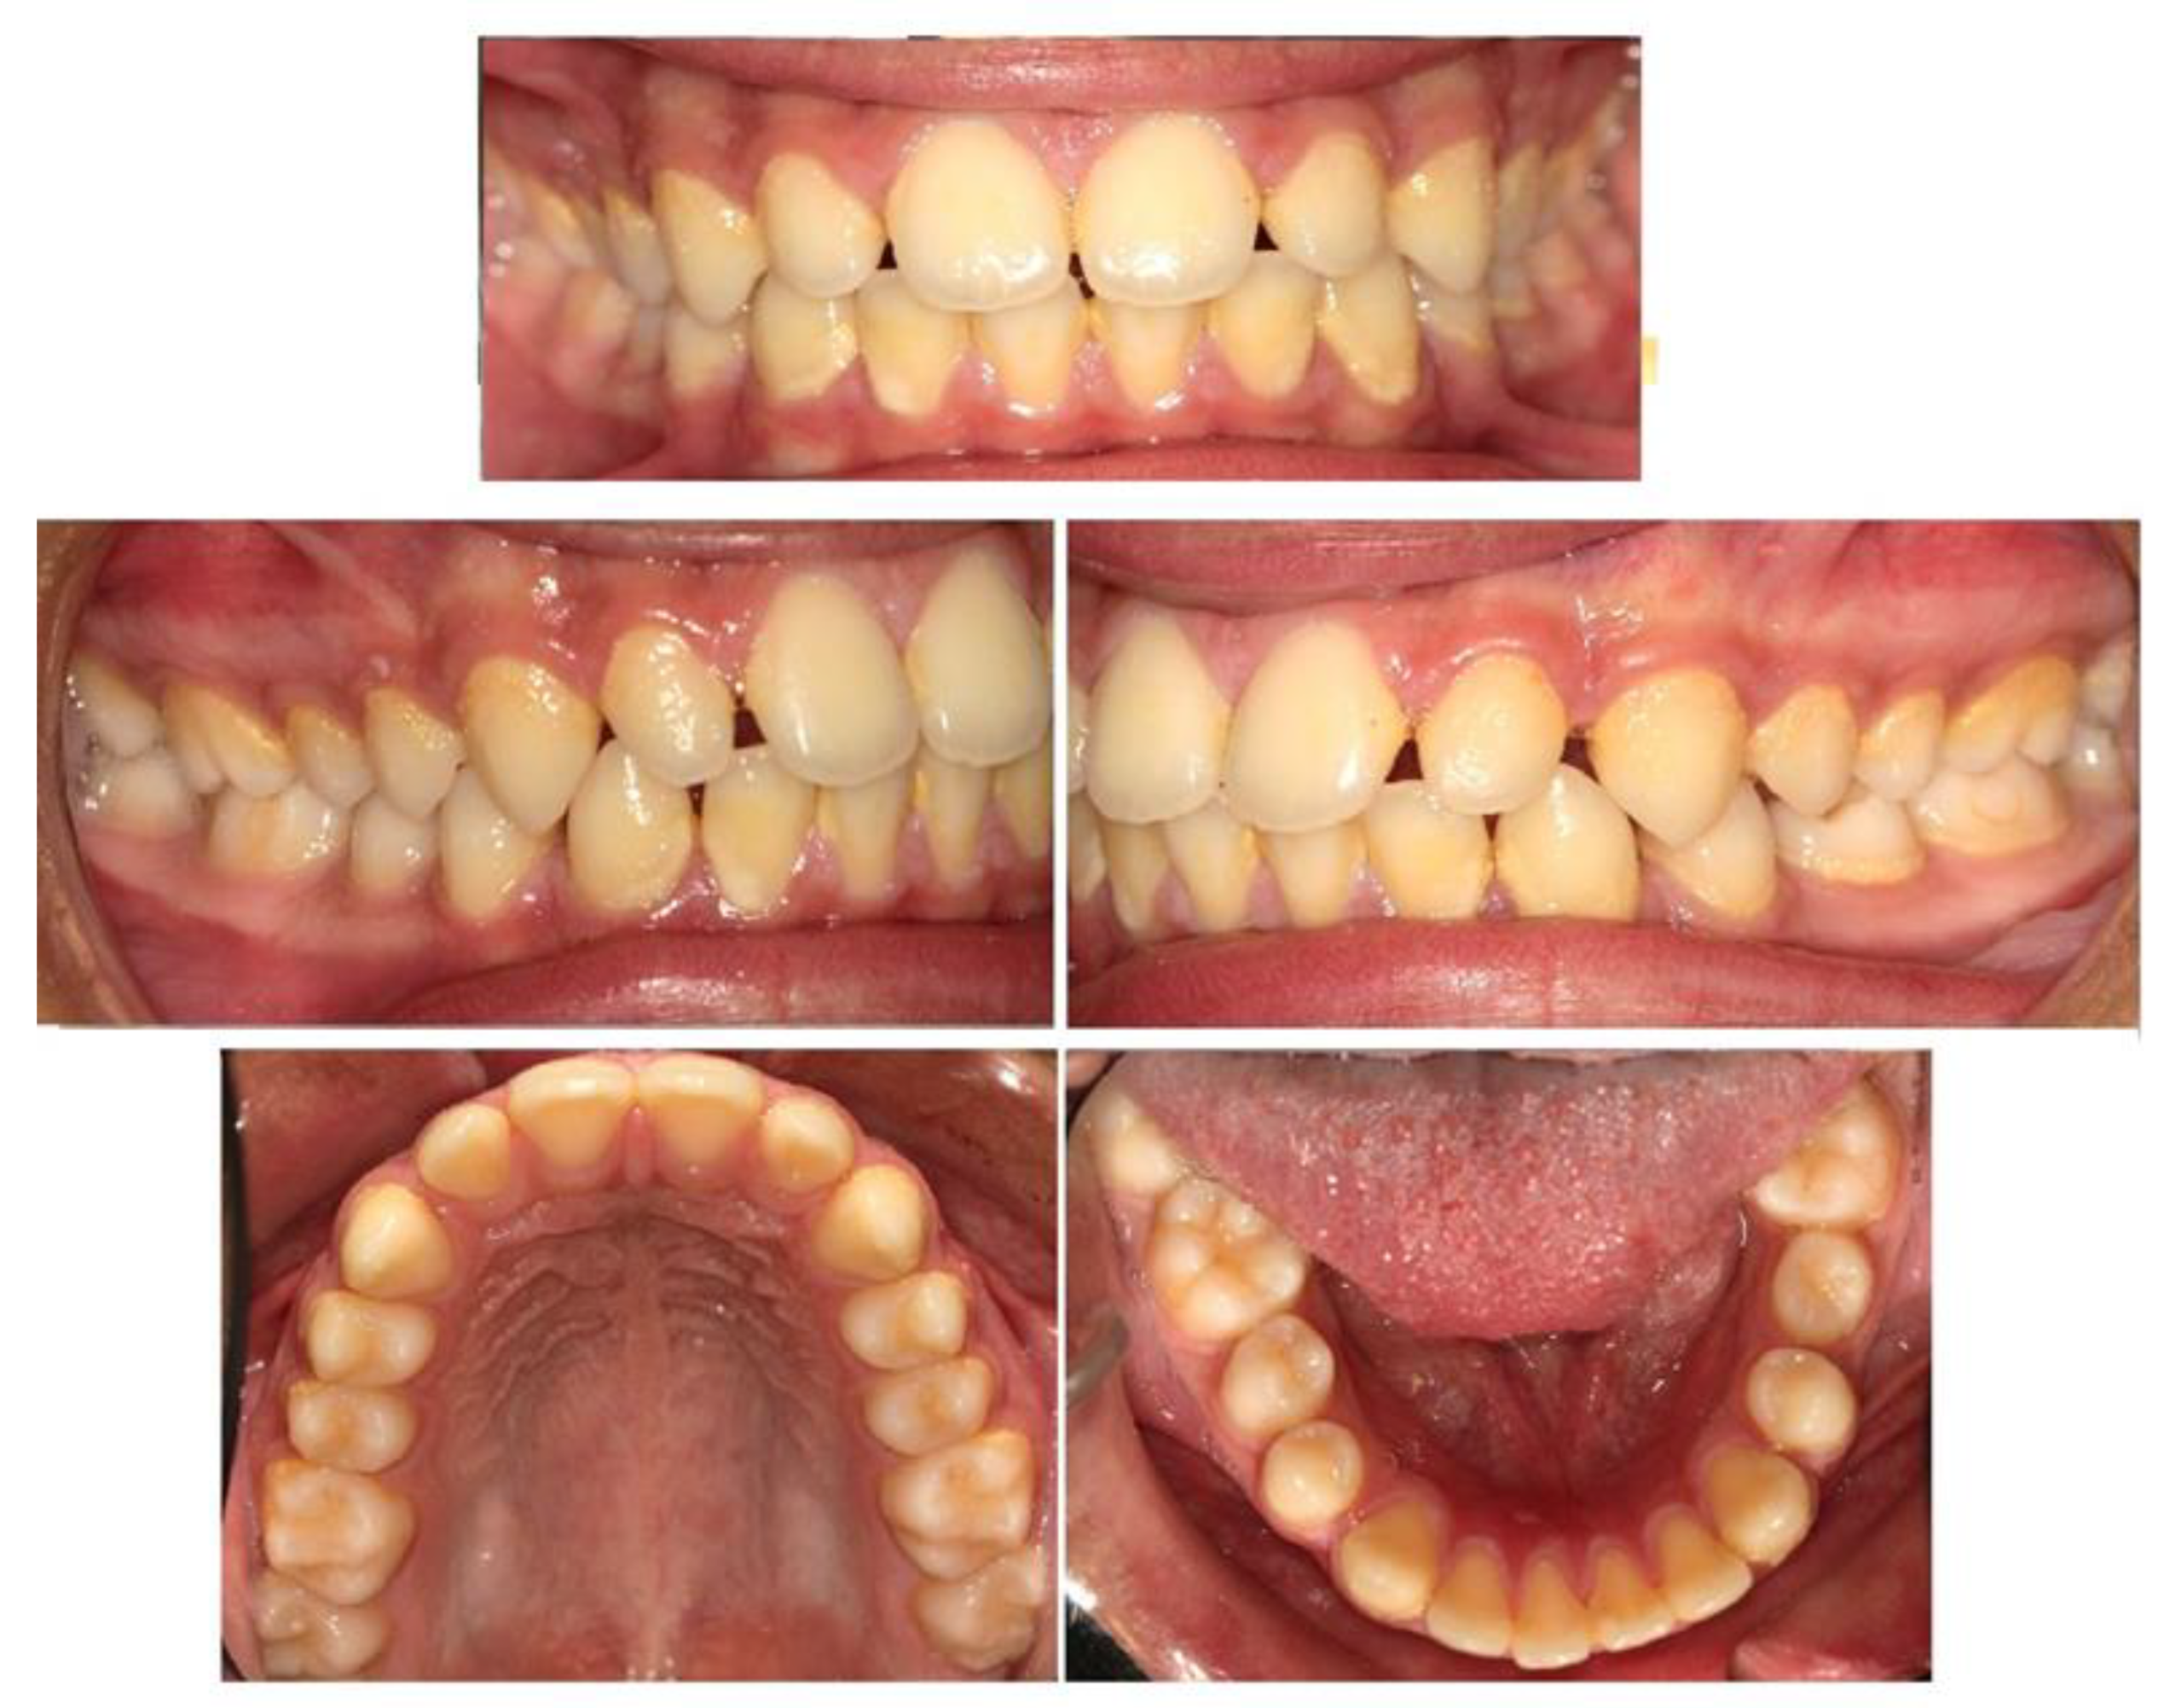

Bimaxillary Dentoalveolar Protrusion Case Treated with Anchorage by Buccally Implemented Mini-Implants Using a 3D-Printed Surgical Guide

3. Results